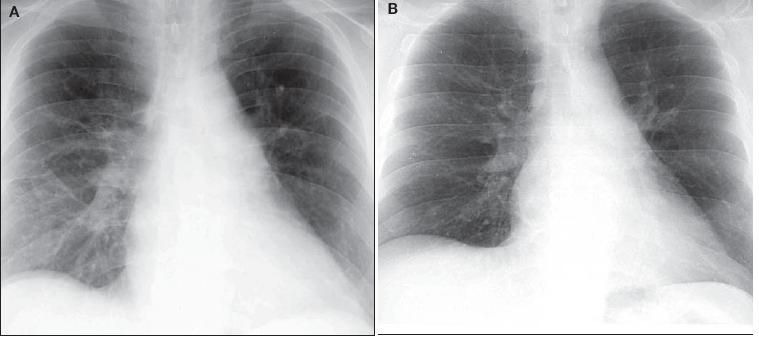

Twelve days after prednisone treatment, there was significant interval improvement in the bilateral opacities previously noted; after 30 days of prednisone, complete radiographic resolution was seen (Figure 3). Two months after moderate-dose prednisone (30 mg daily), a CT scan of the chest revealed complete resolution of both infiltrates and lymphadenopathy.

Figure 3 – Significant interval improvement was detected after 12 days of prednisone treatment (A). After 30 days of prednisone, complete radiographic resolution was seen (B).